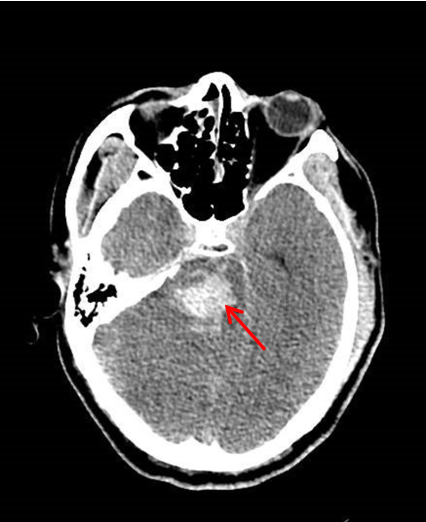

术前颅脑CT可见脑干出血(红色箭头所示)